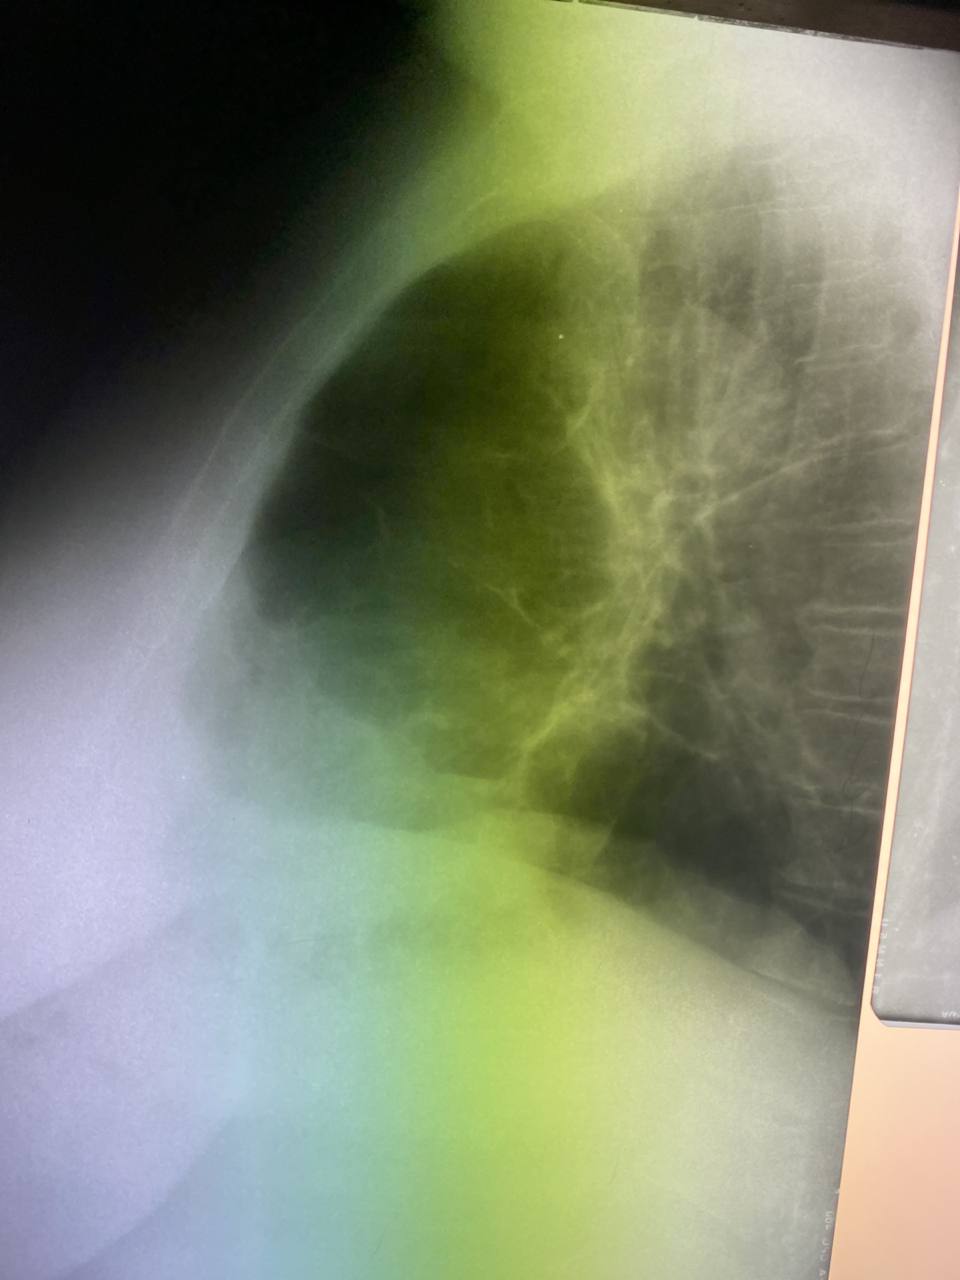

30 лет

Левый бок просится

Может ли это быть колапсом верхней левой доли? Я не вижу люфтзихеля

Серп воздуха вокруг дуги аорты

Ателектаз с выпотом просто?

Ага, странно смотрится. Продинамить надо

Это чисто пневматоракс слевам

В анамнезе булезная эмфизема, пневмоторакс слева 2 дня назад. Пневмоторакс справа давно.  Женщина 51год

Бок